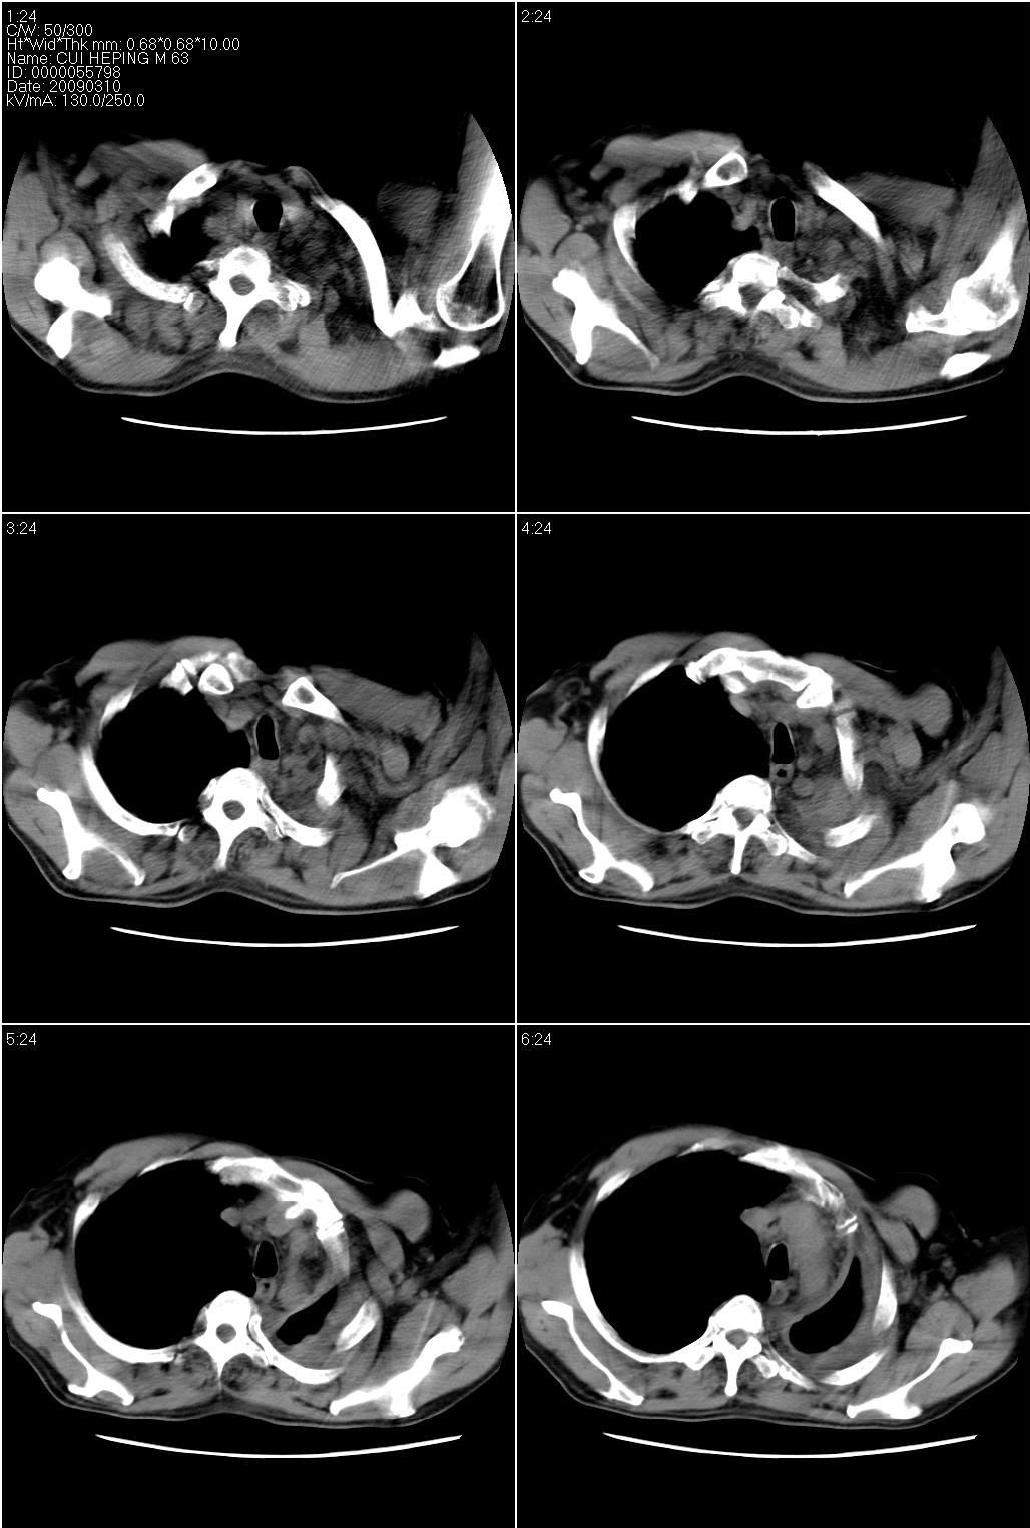

以下是引用随光逐影在2009-3-10 20:54:00的发言:[br]1)左肺结核,左肺膨胀不全。2)左侧液气胸,左侧胸膜肥厚。